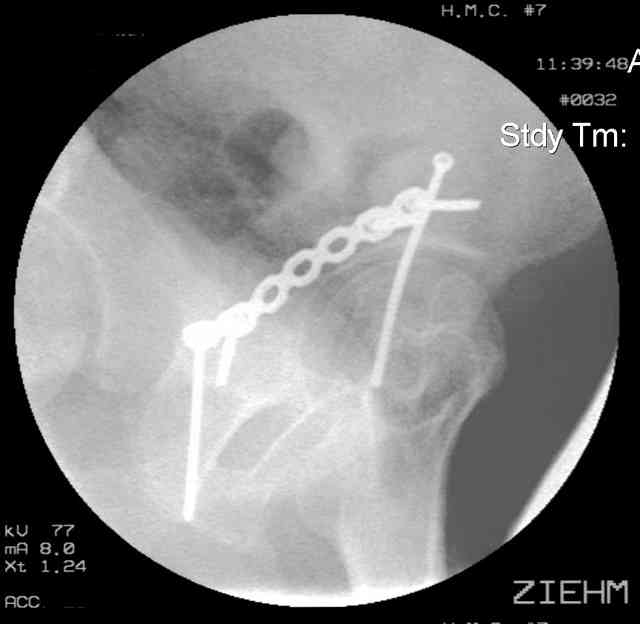

Here's a pic from the foot of the bed and you can see the clamp in the wound and the knee is extended so he must've had a tight rectus. The C-arm is rolled back to an obturator oblique image to reveal the anterior column...we put a slight outlet tilt to combine the images and give a better view of the anterior column...we can see the posterior column limb reduction in the wound, we can palpate the quadrilateral surface limb, and the image demonstrates the anterior column portion...you can adjust the tilt and rotation to image tangentially to the fracture plane if you'd like. We've inserted a 2mm K wire to site the starting point and aim/orientation for the drill and screw

Prone Imaging

same image, just another look.